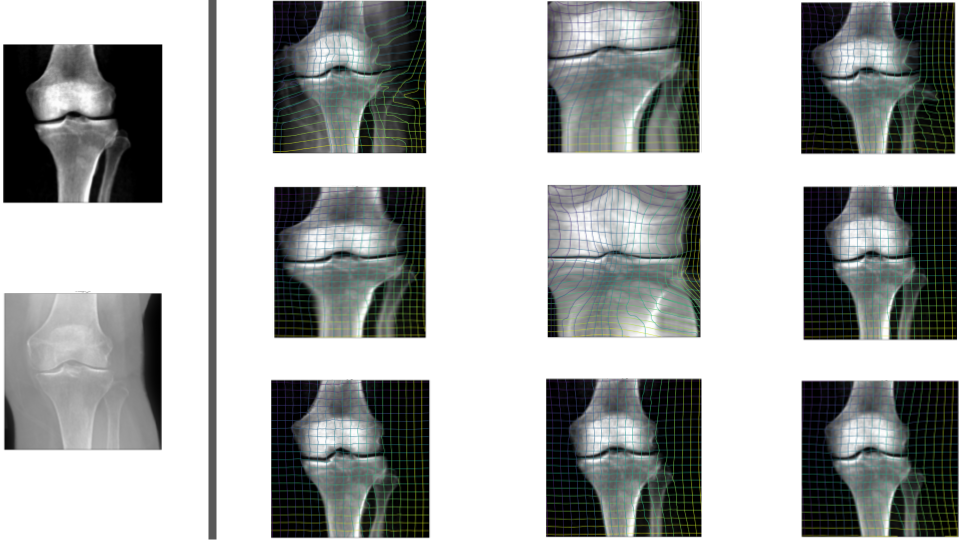

Refer to captionMoving imageFixed imageLNCCMSEMINDNGFDeepSim [6]AE[6] + LNCCVGG[34] + LNCCDINO[4] + LNCCOurs

Figure 4: 2D results. Pixel-based similarity losses fail to capture true correspondences in the "missing anatomy" scenario. Images on the right show the warped moving image which should ideally resemble the fixed image. Our method (Diffusion Features + LNCC) performs the best, as quantitatively shown in Tab. 1. DXA images reproduced by kind permission of the UK Biobank®

4 Multimodal (DXA\rightarrowX-Ray) 2D Knee Registration

We show registration results in Fig. 4 and report Dice scores of bone segmentations and percentage of pixels with negative Jacobian for the registration map, ΦΦ\Phiroman_Φ, in Tab. 1. Conventional methods fail in finding appropriate semantic correspondences in the "missing anatomy" setting. They stretch the bones and fill up the space of soft tissue, which is visible in X-Rays and is missing in DXA scans.

Although other feature extractors (Autoencoder [6], VGG [34], DINO [4]) do not have this issue, the features from off-the-shelf pretrained diffusion models show the best performance (Tab. 1). The combination of LNCC with diffusion features outperforms all other baselines and even the existing state-of-the-art method Seg-Guided-MMReg [7], which was trained with segmentations.